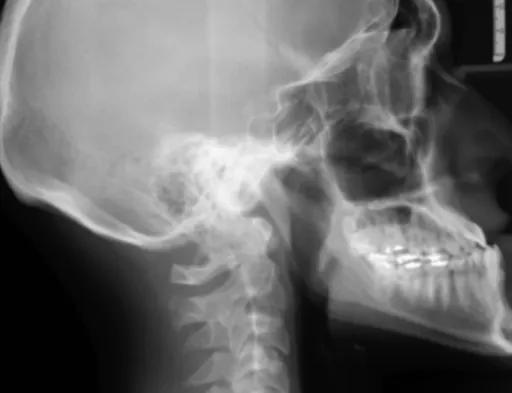

위 천공이 의심되면, 병원에서는 여러 가지 검사를 통해 정확하게 진단하게 돼요. 가장 기본적인 검사는 엑스레이 촬영이에요. 엑스레이를 찍었을 때 복강 내에 공기가 새어 나온 흔적, 즉 '기복증'이 보이는지 확인하는 거죠. 이게 보이면 위 천공 가능성이 매우 높답니다. 물론 엑스레이만으로 100% 확진하기는 어려울 수 있어서, 복부 CT 촬영이나 위내시경 검사를 추가로 시행하기도 해요. CT 촬영은 복강 내 염증 범위나 다른 장기 손상 여부를 더 정확하게 파악하는 데 도움이 된답니다. 치료는 천공의 원인, 범위, 환자의 전반적인 건강 상태에 따라 달라져요. 하지만 대부분의 경우, 천공 부위를 빨리 막고 복강 내 오염을 제거하는 응급 수술 이 필요해요. 복강경 수술이나 개복 수술을 통해 천공 부위를 봉합하거나, 손상된 부위를 절제하고 위장 재건술을 시행하기도 하죠. 수술 후에는 항생제 치료와 함께 위산 분비를 억제하는 약물 치료 등을 병행하면서 회복을 돕게 돼요. 수술 시기를 놓치면 복막염, 패혈증 등 심각한 합병증으로 이어질 수 있기 때문에, 위 천공 증상 이 의심된다면 주저 말고 바로 응급실로 가셔야 해요!